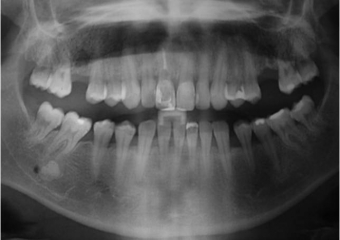

Imagem inicial de paciente com fratura de raiz no dente 11

Raio X inicial